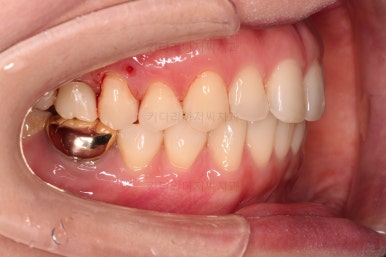

어금니가 문제였습니다.

윗니 어금니가 하나 없는 상태였고요.

어금니가 없이 지낸지 꽤 시간이 흐른터라 뒤쪽 어금니가 앞으로 쓰러져 공간을 잠식하고 있었습니다.

물론 현재 모습대로 임플란트를 할려면 할 수 있지만 장기적으로 쓰러진 치아를 계속 사용하는게 치아수명에 바람직 하지 않죠.

임플란트도 원래 들어가야 할 어금니의 크기보다 많이 장가서 기능적으로 좋지 못하고요.

어금니쪽은 쓰러진 어금니를 원위치 시키기 위해서 미니스크류를 식립하여 준비작업을 해줍니다.

어금니도 원위치로 많이 갔네요.

아랫니 부분교정과 어금니 부분교정은 비교적 조기에 끝났으나(7개월) 임플란트가 생각보다 오래 걸렸습니다.

적절한 공간 확보 이후 해당 부분의 뼈가 너무 얇아 임플란트를 하기에 부적절했던거죠.

상악동 거상술 + 골이식을 광범위하게 꽤 많은 양을 하고, 한참을 기다립니다.

이후에 적절한 시기에 임플란트 식립을 하고 보철을 하고 마무리를 합니다.